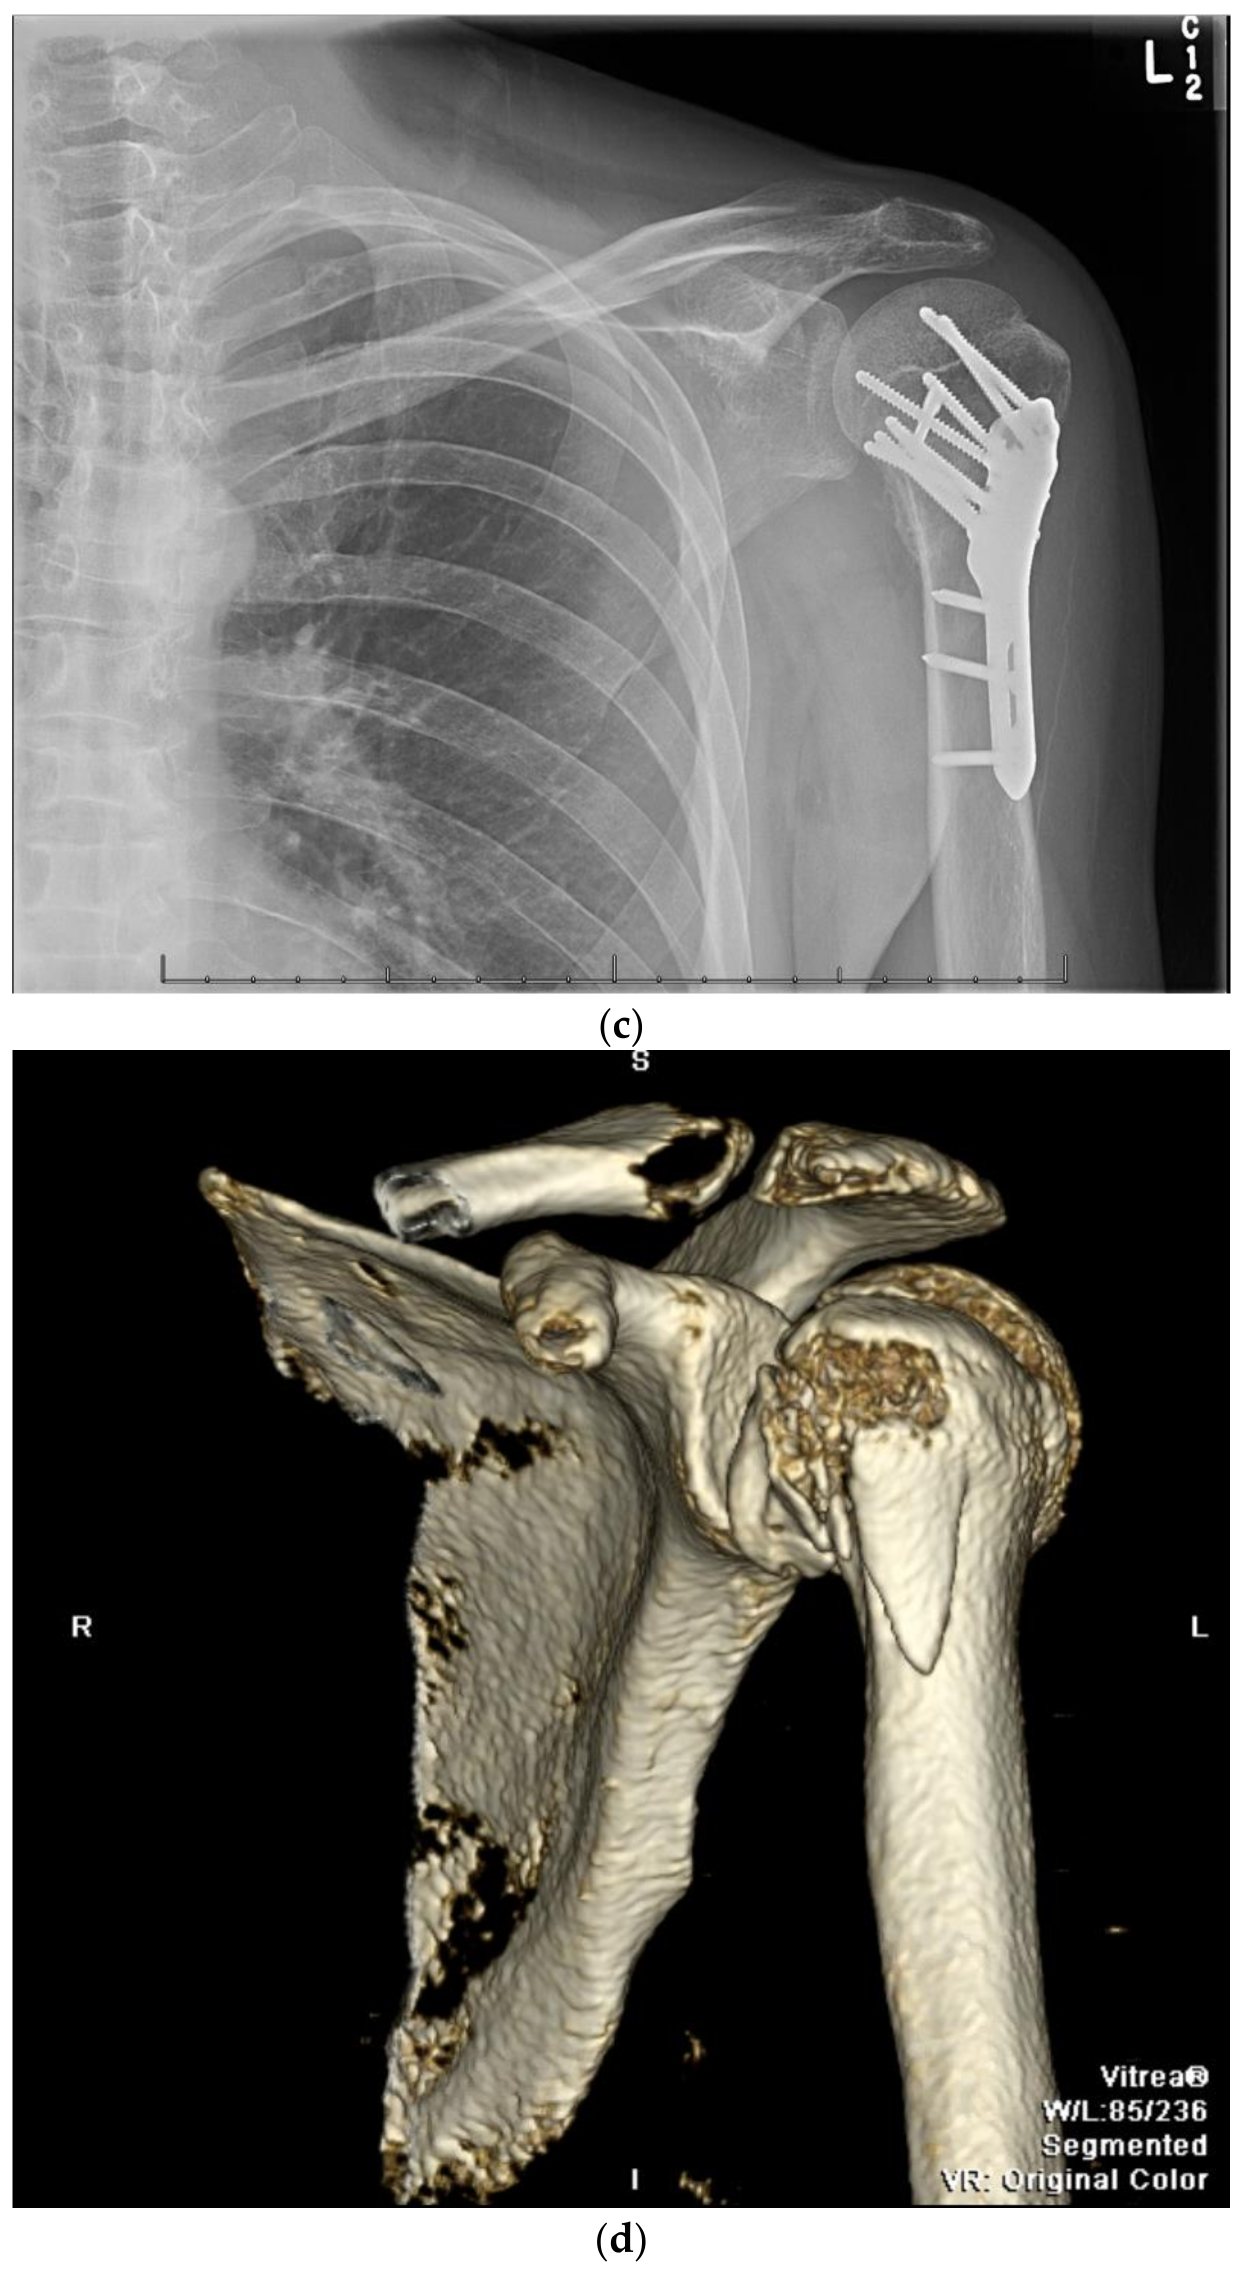

9. Open Reduction and Internal Fixation

10. Surgical Approach

10.2. Surgical Technique

10.3. Fracture Reduction

10.4. Fracture Fixation